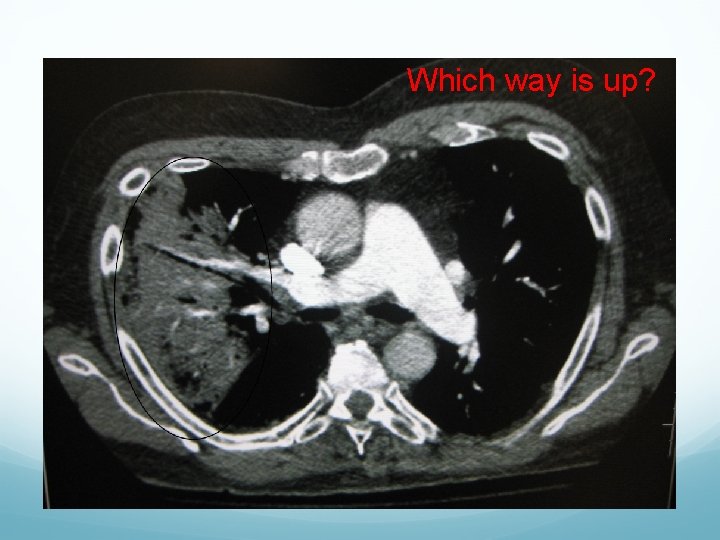

Which way is up?

Which way is up? HUH?

What the $@#% is this? Which way is up? HUH?